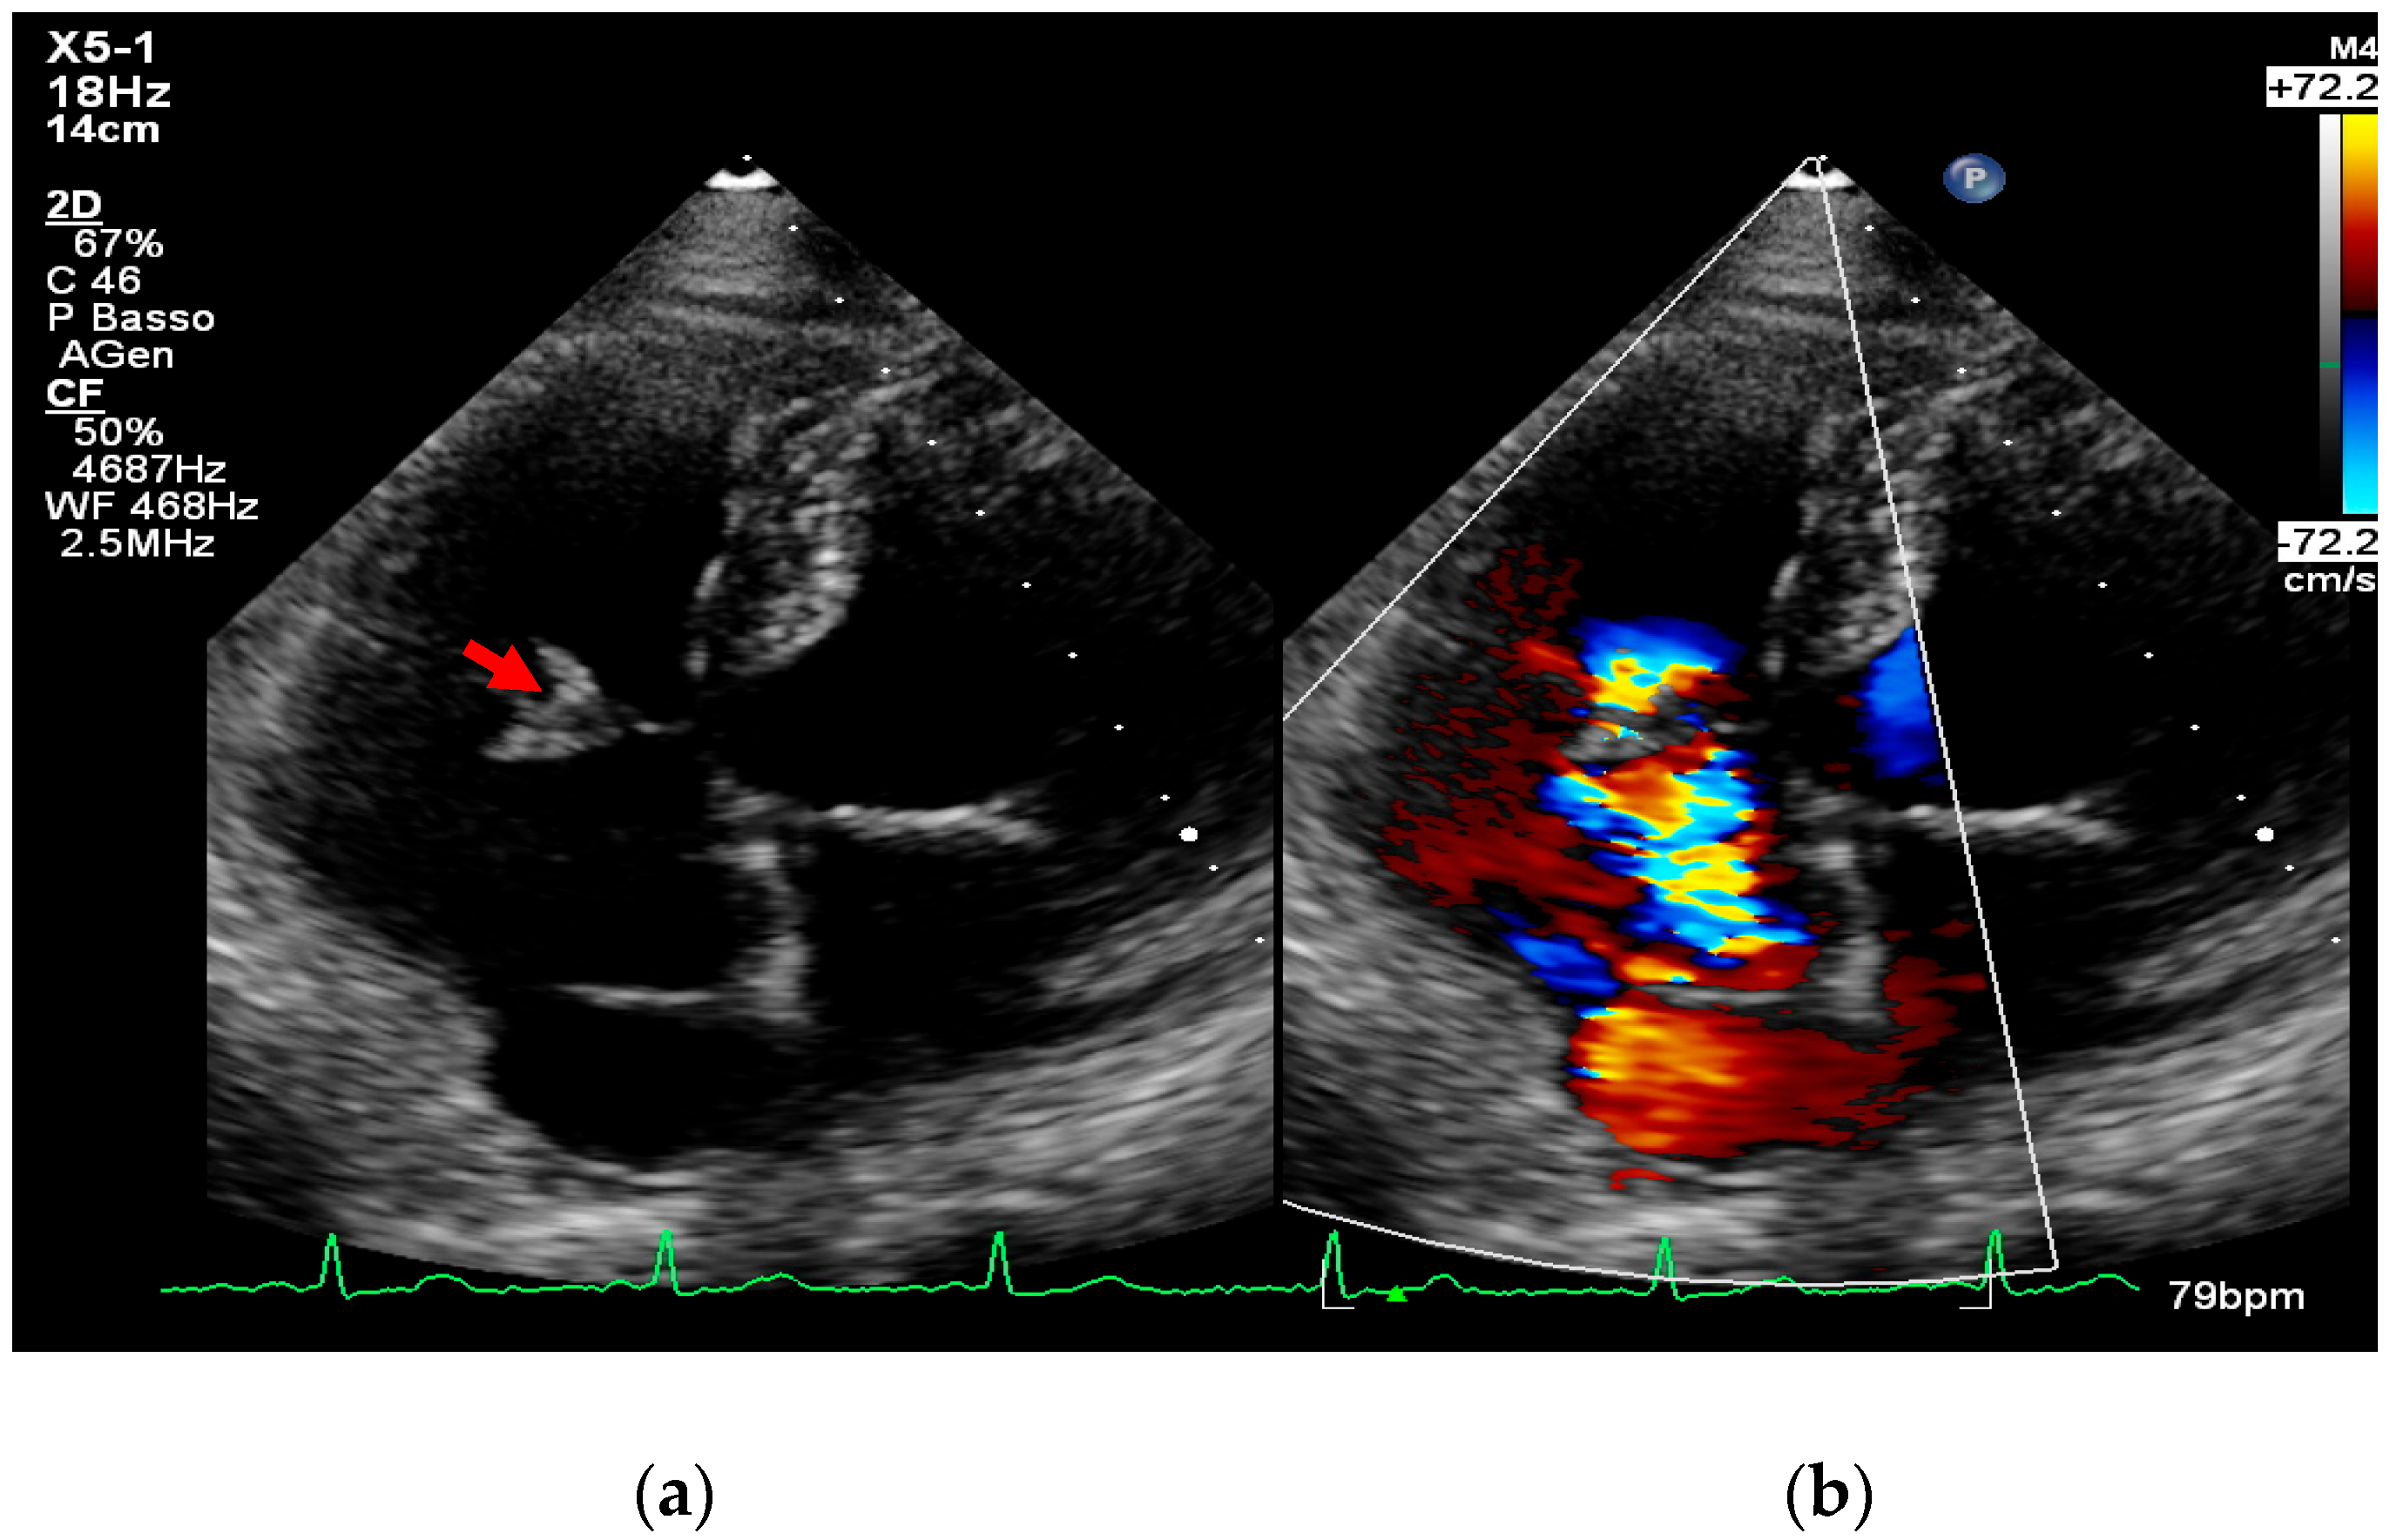

4. Echocardiography

- valvular or leaflet perforation, i.e., tissue defects causing valvular regurgitation originating from the site of perforation.

- intracardiac fistula, visualized as an abnormal communication between cardiac chambers or vessels, is often detected by using color Doppler.

- significant new valvular regurgitation compared with previous imaging, i.e., increase in regurgitant jet size, vena contracta width…

Differential Diagnosis